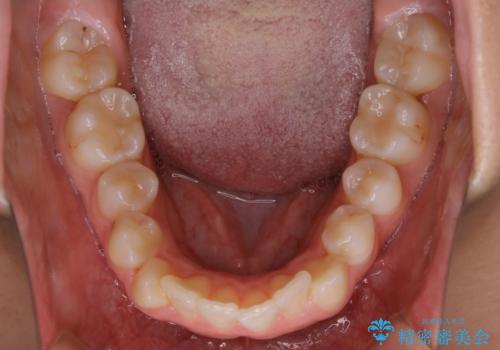

ガタつきの度合いは軽度でしたが歯列の幅が狭く、その分前歯が上下とも前方に出てしまっていました。

しっかりと口元・顔貌まで変化を起こせるように上下左右の第一小臼歯を抜歯し、ワイヤー装置にて矯正を開始することとなりました。